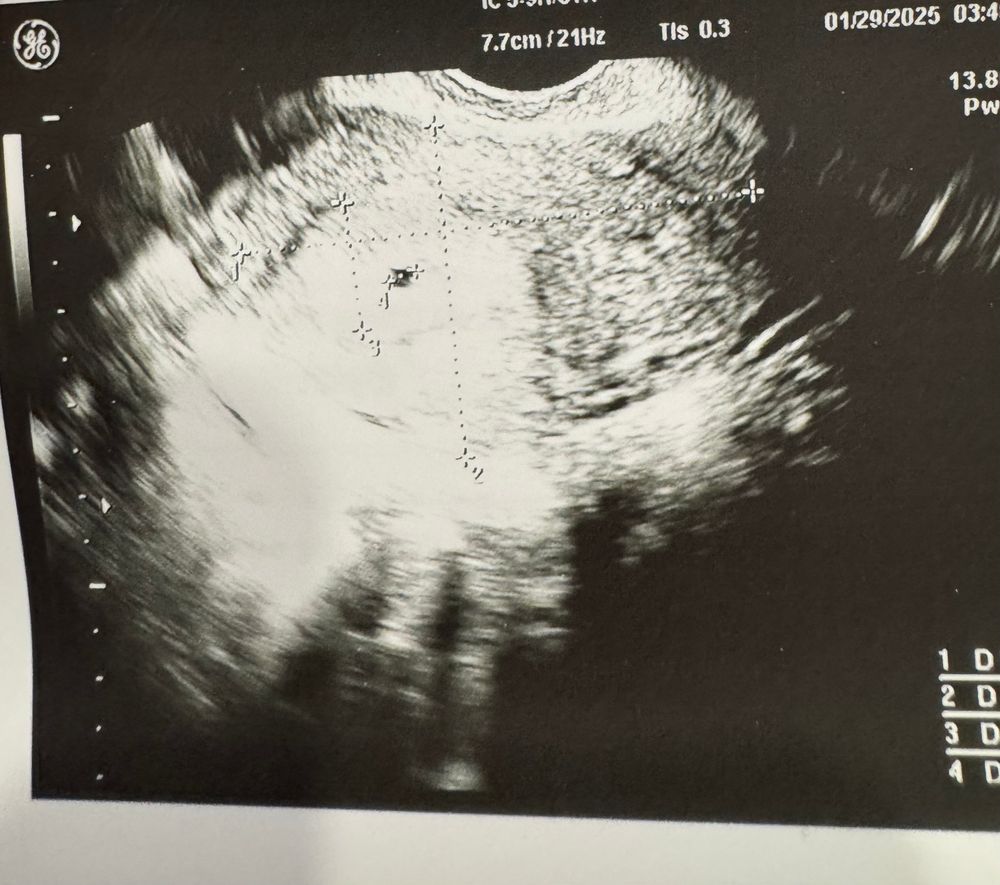

Результаты УЗИ 32 д.ц